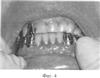

На фигуре 4 изображен временный протез с мягким слоем «Coe-Soft» GC в полости рта.

Коррекцию протеза осуществляют непосредственно в полости рта с помощью эластичной пластмассы «Coe-Soft» GC на следующие сутки после оперативного вмешательства, когда уже началось заживление операционной раны, снижение отечности и болевой чувствительности за счет стимулирующего действия аутоплазмы (фиг.2). Этот факт позволяет беспрепятственно изготовить мягкий слой непосредственно в полости рта, который будет максимально точно повторять рельеф протезного ложа, а следовательно, и равномерно распределять жевательную нагрузку. Для этого на внутреннюю поверхность базиса протеза стерильным шпателем наносят приготовленную согласно инструкции фирмы производителя эластичную пластмассу «Coe-Soft» GC. Затем протез фиксируют в полости рта в положении центральной окклюзии. После полимеризации протез извлекают, обрезают избыток материала и накладывают на постоперационный дефект (фиг.3, 4).